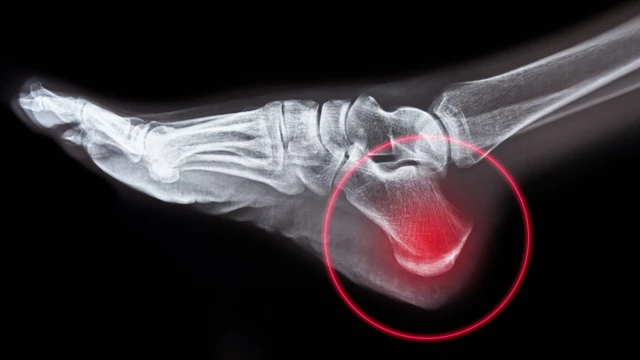

Viêm đầu xương gót hay còn gọi bệnh Sever, là một trong những nguyên nhân phổ biến nhất gây đau gót chân ở trẻ đang lớn, đặc biệt là trẻ hoạt động thể chất nhiều. Đó là tình trạng viêm của đĩa tăng trưởng ở xương gót chân. Viêm đầu xương gót là do quá trình căng thẳng lặp đi lặp lại ở gót chân. Bệnh thường xảy ra nhất trong giai đoạn tăng trưởng nhanh, khi xương, cơ, gân và các cấu trúc đang thay đổi nhanh chóng.